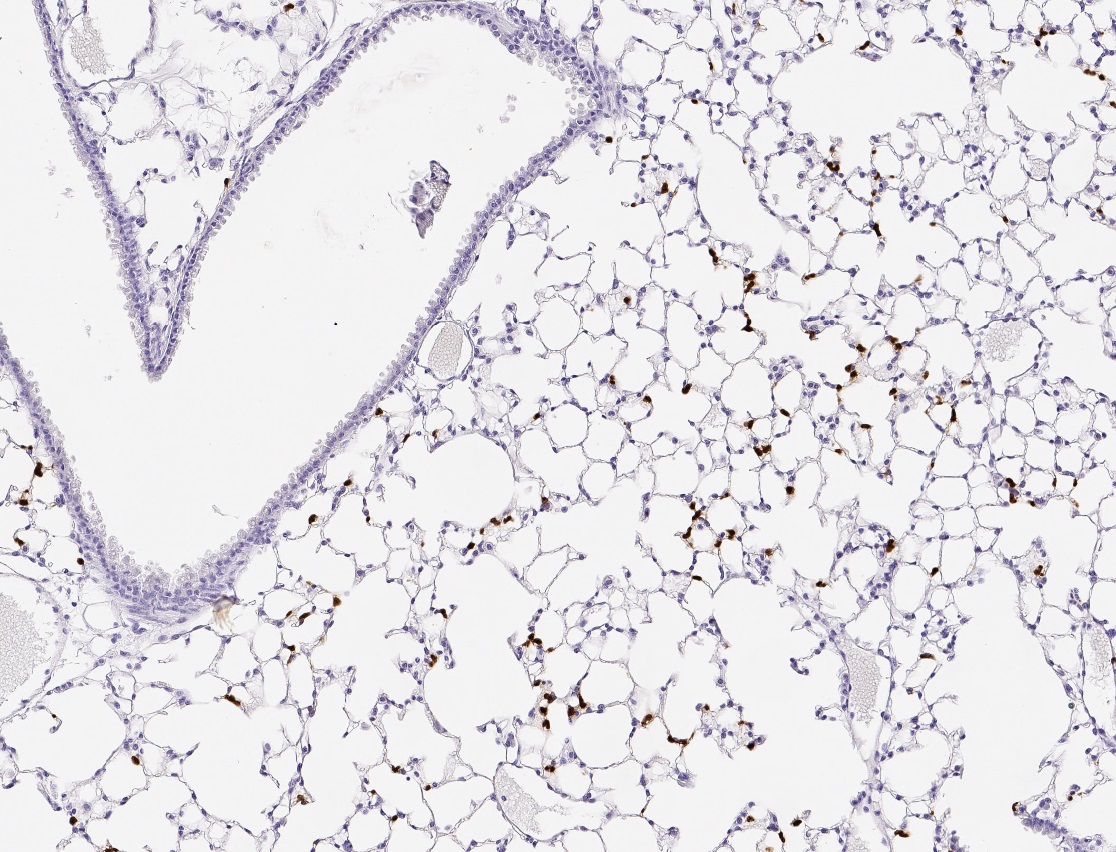

The FDA approval of AI-based tools in digital pathology signifies a critical milestone. With these tools, pathologists can quickly assess cellular markers indicative of cancer progression or response to therapy. For example, analyzing the expression of markers like PD-L1 and CD47 in NSCLC can help determine the suitability of specific immunotherapies. Pathology slide scanners offer a streamlined approach to capturing these data points, which are crucial in personalizing treatment plans.

A recent study highlights the effectiveness of ADNs in treating NSCLC by targeting two specific proteins, PD-L1 and CD47. These proteins play significant roles in cancer cell survival by evading immune system recognition. PD-L1 suppresses effector T-cell activity, while CD47 interacts with macrophages, issuing a “do not eat me” signal that protects cancer cells from being attacked. By using antibodies, that block both PD-L1 and CD47, on the surface of nanoparticles, researchers have created a therapeutic agent that can both activate T-cells and inhibit tumor growth.

Pathology slide scanners play a crucial role in identifying patients who could benefit from ADN-based therapies. Scanners equipped with analysis software and AI tools can help rapidly assess PD-L1 and CD47 expression levels, determining whether a patient is a suitable candidate for this type of treatment. This capability is particularly beneficial given the heterogeneity of NSCLC; not all patients express these markers at levels that would make them responsive to ADN therapies.

Moreover, slide scanners contribute to a more accurate prognosis by quantifying marker expression across entire tumor tissue sections. With this comprehensive digital analysis, pathologists can distinguish between high-expressing and low-expressing regions, thereby refining the precision of treatment strategies. This targeted approach is especially critical for NSCLC, where the effectiveness of immunotherapies varies widely depending on individual tumor biology.